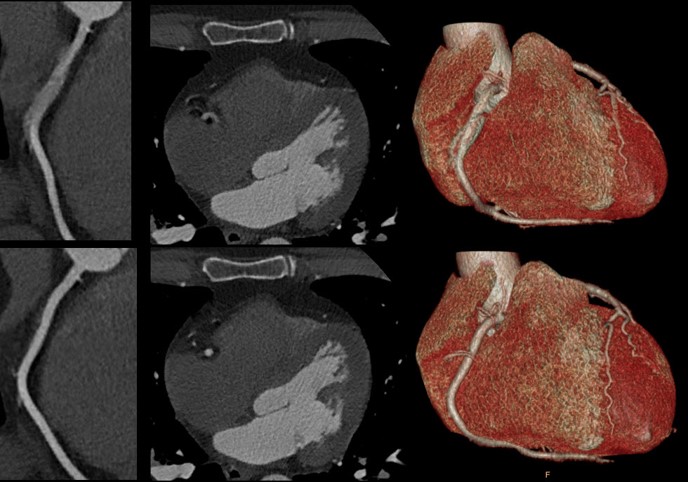

- Spectral CT 7500 Motion in Right Coronary Artery Comparison

Spectral CT 7500 expands on Philips proven spectral-detector benefits to now include additional patient populations that were not previously served. The spectral insights are available for all patients, from pediatric to bariatric, and for any clinical indication, including challenging cardiac scans with high and irregular heart rates, without compromising image quality, dose or workflow. The spectral workflow enables radiologists to optimize reading with rich spectral results and AI-based smart tools available in any reading environment with Spectral Magic Glass on PACS.